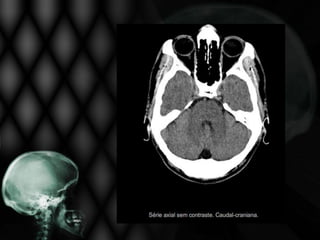

• Paciente de 78 anos, hipertenso, apresenta início súbito

de perda da força muscular à direita, com desvio de rima

bucal e sinais piramidais também à direita. É incapaz de

deambular e sua fala está arrastada e praticamente

ininteligível há 6 horas;

• Solicitou-se TC de crânio.

Não se visualiza nesta TC de crânio:

Edema cerebral

Sangramento na periferia do 4º ventrículo

Hipodensidade frontal direita extensa

Foco de sangramento no interior da área

isquêmica